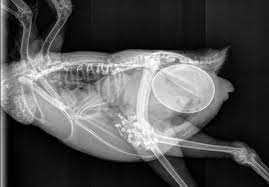

دامپزشک منخصص پرندگان  معمولاً قادر به احساس تخم  با لمس و مشاهده شکم متسع است. معاینه کامل بدنی شامل بررسی چشم ، پوست ، منقار ، پا ، وزن  بدن ، تاج ، سوراخ های بینی ، پر ، سینه ،چینه دان ، بال ، غدد و مخرج  است. ضروری ترین روش تشخیصی رادیوگرافی (اشعه ایکس) است زیرا بیشتر تخم ها حاوی مقدار زیادی کلسیم هستند و به زیبایی خود را نشان می دهند. با این حال ، اگر اشعه ایکس نتیجه ای نداشته باشد ، ممکن است سونوگرافی انجام شود. علاوه بر این ، یک CBC ، مشخصات بیوشیمیایی پلاسما و سطح کلسیم یونیزه و کلسیم توتال  باید بررسی شود.